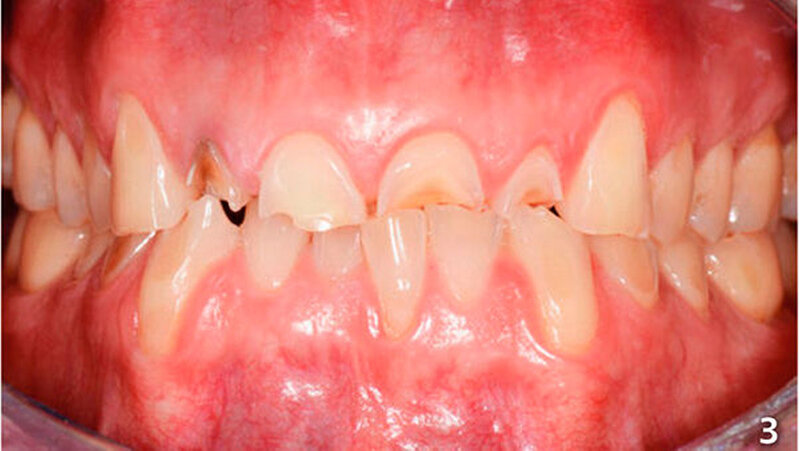

Ein 42 Jahre alter Patient, der an der Klinik für Präventivzahnmedizin, Parodontologie und Kariologie der Universität Zürich vorstellig wurde, gab an, unter gastro-ösophagealem Reflux (GERD) und Asthma zu leiden. Zur Therapie des Asthmas nahm der Patient seit circa zehn Jahren mindestens zweimal täglich ein Asthmaspray. Es ist bekannt, dass GERD Asthmasymptome verschlimmern kann, und dass wiederum Asthma sowie einige Asthmamedikamente GERD-Symptome verstärken können (Thomas et al. 2010; Hom & Vaezi 2013; Pauwels 2015).

Der Patient wies an allen Frontzähnen sowie an den Seitenzähnen des Unterkiefers starke erosive Defekte auf (Abb. 1-3). Der Patient störte sich vor allem am Erscheinungsbild seiner Oberkieferfrontzähne und dem Engstand im Unterkiefer-Frontzahnbereich. Er wurde über verschiedene Therapiemöglichkeiten ausführlich aufgeklärt und entschied sich für direkte Rekonstruktionen mit Komposit. Im Februar 2016 erfolgte die Versorgung mit Kompositrestaurationen, wie folgt beschrieben.